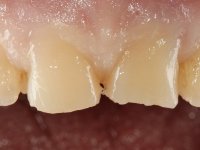

It was important to involve the patient in assessing the aesthetic advantage of increasing the height of central superior incisors. For this purpose, a direct mock-up was molded in-mouth, with non-adhesive composite resin. Once the patient agreed to the course of treatment, a silicon matrix was prepared, for subsequent production of provisional veneers. After installing a gingival deflection cord, dental preparation was performed, with special consideration to the fact that the insertion of both veneers would be frontal. Accordingly, mesial and distal walls did not require convergence. The incisal edge was prepared perpendicular to the axis of insertion. After preparation, IDS (immediate dentin sealing) was carried out. A “one-step, double mix technique” was adopted for impression, using putty soft and light silicon. Provisional veneers were produced using dual polymerization composite resin. Color selection was done in the same session.

The suggested treatment consisted of two feldspathic ceramic veneers, with frontal insertion and incisal coverage.